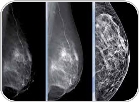

اهمیت ماموگرافی در زنان جوان

بر اساس بررسی‌های انجام شده، اکثر مرگ و میرهای ناشی از سرطان سینه در زنان جوانی اتفاق می‌افتد که ماموگرافی منظمی ندارند. ادامه>>